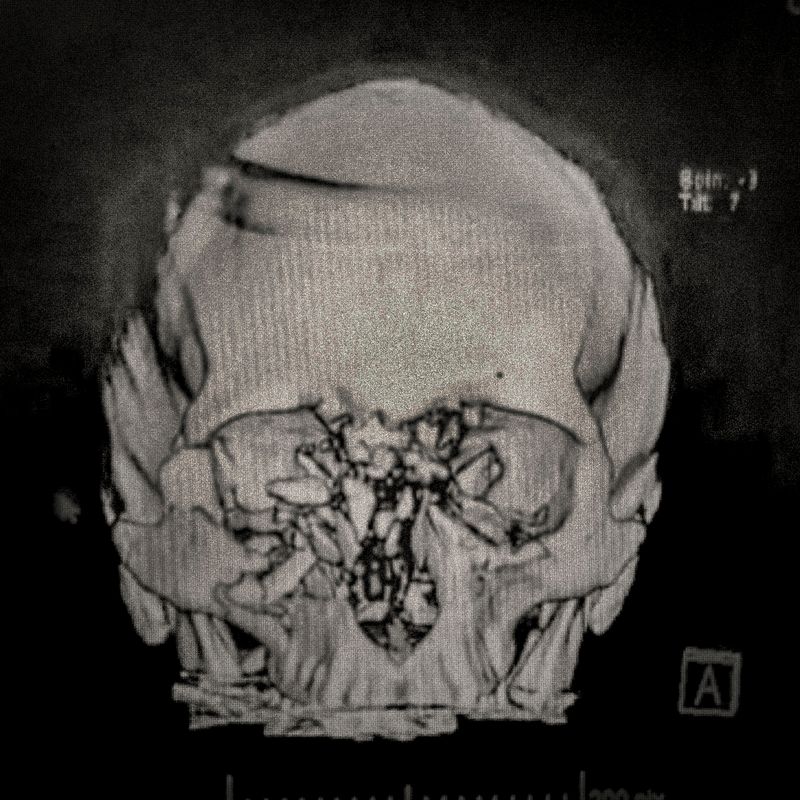

X ray showing the embedded pellet of Camilo Galvez (24) injured by chilean police during Santiago protests.